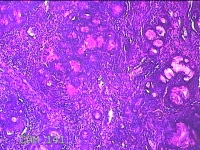

左侧鼻腔病变组织

性别

男

年龄

28岁

临床诊断

1.慢性鼻窦炎 2.鼻中隔偏曲 3.变应性鼻炎

一般病史

反复鼻塞10余年,加重伴脓涕3天。

标本名称

大体所见

灰白暗红色组织0.8x0.3x0.2cm一块,表面糜烂,内有少许骨质。